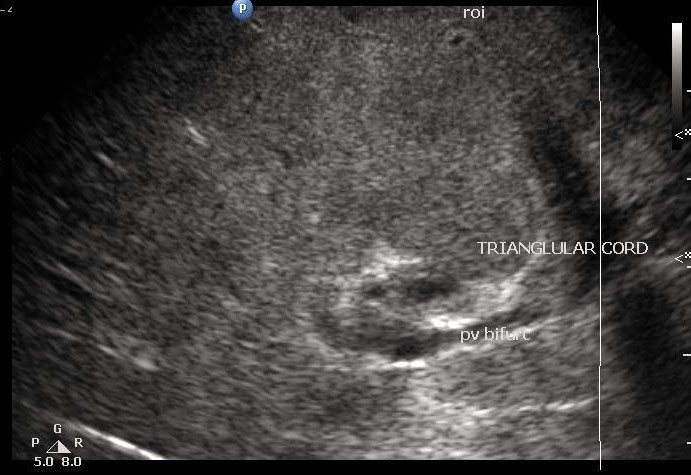

A positive triangular cord sign is hallmark of the biliary atresia.

Triangular cord sign is a thick tubular or triangular echogenic density (fibrous ductal remnant) along the anterior aspect of the portal vein at its bifurcation into the right and left branches.

Presence of triangular cord sign

Positive of triangular cord sign = thickness of EARPV > 4 mm on a longitudinal scan

(EARPV - echogenic anterior wall of the right portal vein)